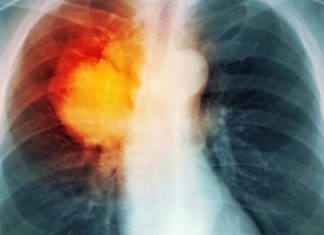

Sëmundja e frikshme e mushkërive që prek më shumë gratë se burrat

Sëmundja pulmonare obstruktive kronike (SPOK) është konsideruar gjithmonë si sëmundje e meshkujve, ndërkohë që aktualisht po vret më shumë gra sesa burra. Gati 8% e e grave në Amerikë janë diagnostikuar me këtë sëmundje,...